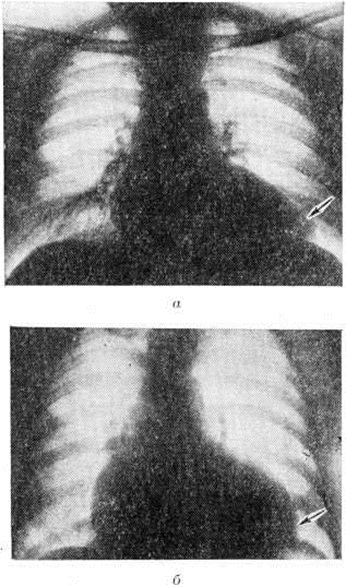

Рис. 10.

Рентгенограммы органов грудной клетки (прямая проекция): а — больного миокардитом Абрамова — Фидлера; тень сердца значительно увеличена в поперечнике, верхушка заострена (указано стрелкой), сердце как бы распластано на диафрагме; б — больного с субаортальный стенозом; тень сердца резко увеличена, верхушка закруглена (указано стрелкой).

Миокардит Абрамова — Фидлера по своей клинические, картине практически неотличим от идиопатической застойной кардиомиопатии (смотри полный свод знаний), а нередко и от идиопатической гипертрофии миокарда, в частности от субаортального стеноза. В пользу Миокардит говорит связь начала или обострения заболевания с инфекцией (чаще вирусной), приёмом лекарственных средств и другими аллергизирующими факторами. Наличие признаков воспаления и аллергии, особенно обнаружение в крови антител к миокарду, делают диагноз миокардита Абрамова — Фидлера более достоверным, хотя отсутствие их не исключает его возможности. Течение миокардита Абрамова — Фидлера более острое (недели, месяцы), кардиомиопатий — более затяжное (годы и даже десятилетия), хотя в результате разработки методов лечения появились подострые и хронический формы миокардита Абрамова — Фидлера. При дифференциальной диагностике с субаортальным стенозом ведущую роль играют данные рентгенологическое исследования (рисунок 10), особенно вентрикулографии, а также эхокардиографии (наличие асимметрической гипертрофии межжелудочковой перегородки). Миокардит Абрамова — Фидлера, в клинические, картине которого преобладает болевой синдром, нередко приходится дифференцировать с острым инфарктом миокарда при ишемической болезни сердца; вместе с тем боль при Миокардит может быть действительно связана с некрозом миокарда, характерным для этой формы.